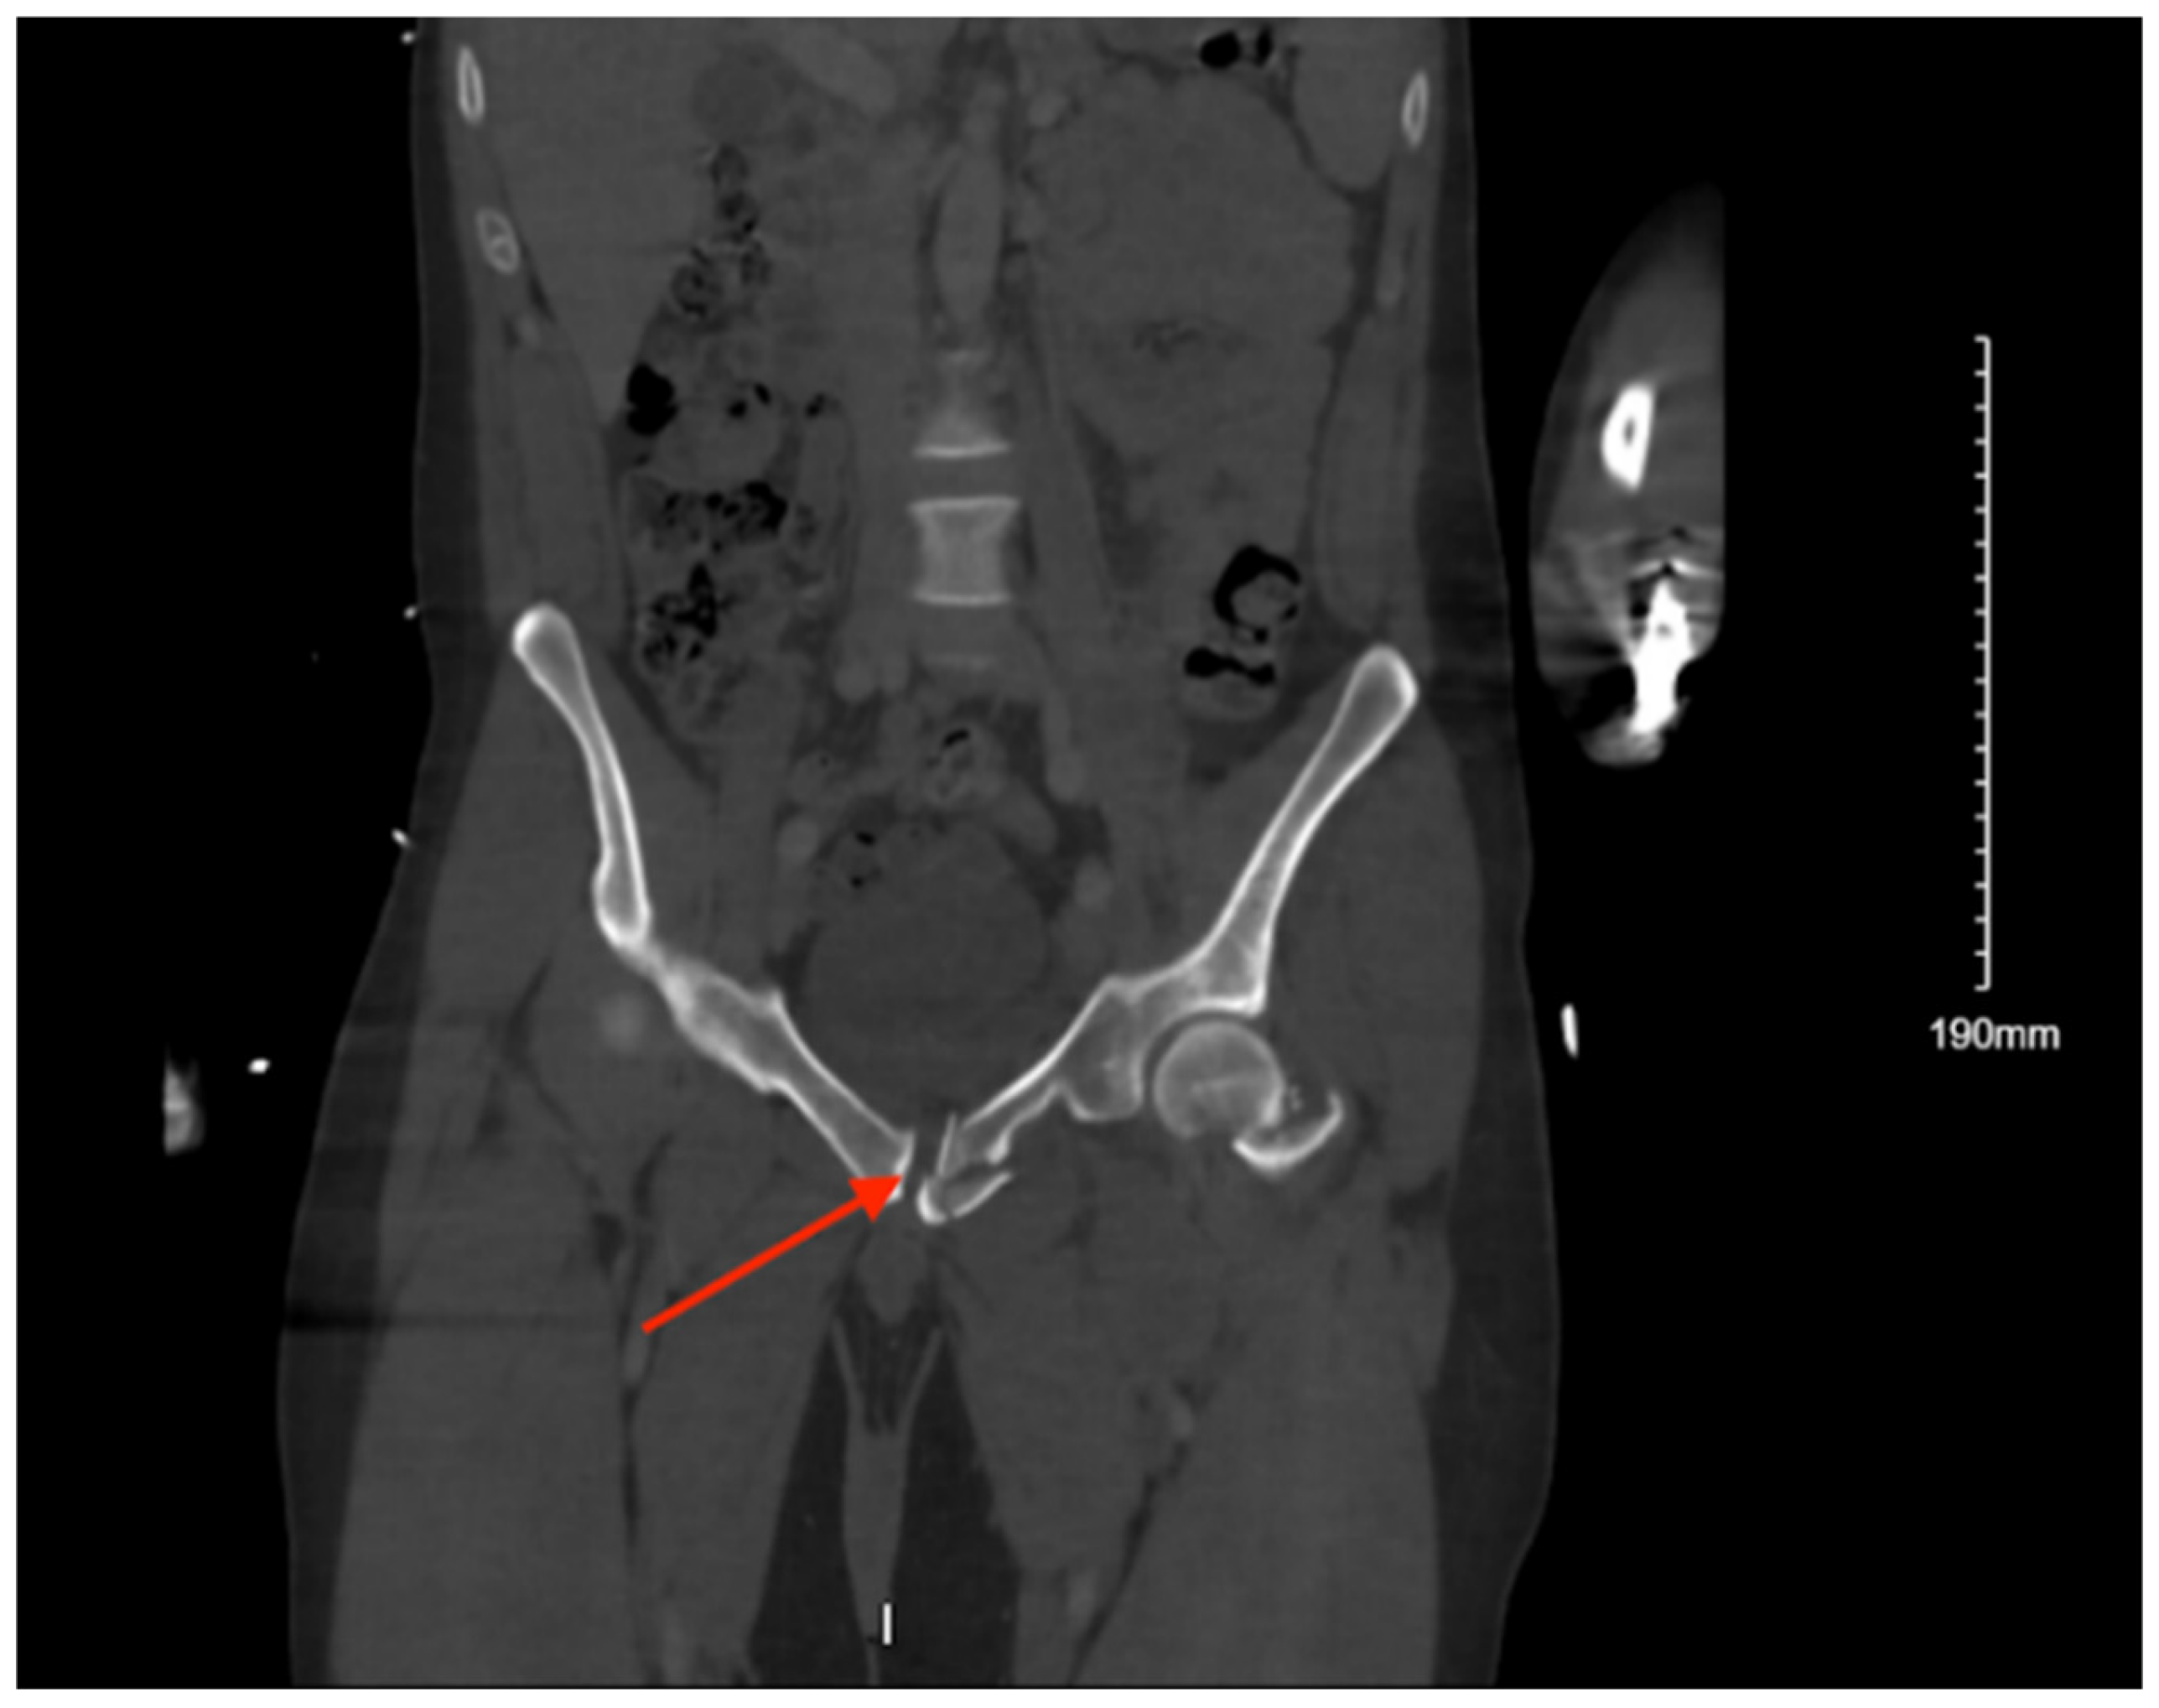

3.9.2. Imaging

Pelvic imaging showed an acute fracture of the left superior pubic ramus near the symphysis and the bilateral inferior pubic rami and an acute fracture of the anterior aspect involving the lateral mass of S1 (Figure 9). She was also found to have a subcapital fracture of the right hip and a fracture involving the anterior aspect of the vertebral body of L5.

Figure 9. CT abdomen/pelvis images of the described fractures in case 9. Red arrows are used to indicate the location of pelvic fractures for easier identification.